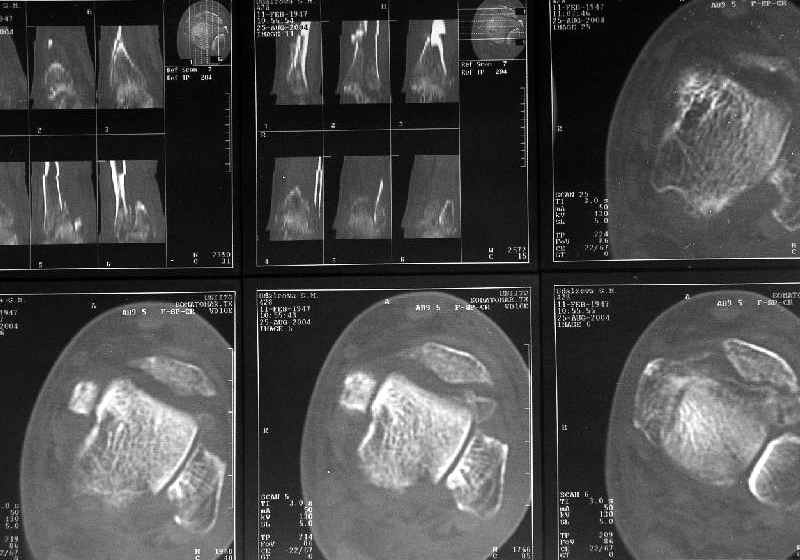

Дама 56 лет 6 недель назад получила спиральные переломы дистальных отделов костей голени. По месту жительства наложили гипс.

Сейчас вот, получается, спохватились. Снимки и КТ в приложении. Какой вариант тут предпочтительнее - открытая мобилизация, репозиция и внутренняя или наружная фиксация? Или ограничиться только резекцией костного шипа над шейкой тарана?Заранее спасибо.A female 56 y.o. 6 weeks ago sustained a fracture of the distal tibia/fibula. At the initial hospital a plaster cast was applied. Now she was referred to our unit. At the moment there is no pain, no obvious mobility. Images and CT attached.What is the best option here? Mobilize the fracture, perform open reduction and internal or external fixation? Or just to cut the anterior spike over the talar neck? THX in advance.

Однако именно по КТ как раз сложнее всего оценить состояние консолидации.

Какова роль КТ при переломах диафиза длиннных костей:

- оценка положения отломков

- оценка сращения и пр.

В нашей, например, практике - никакая. То есть для диафизарных переломов - не пользуемся, т.к. необходимости не испытываем. Суставы, таз - другое дело.

Оно избыточно. Обычная рентгенография дает все, что надо, для оценки диафизарного перелома.

Здесь повреждение не диафизарное, смотрели состояние суставного конца кости и взаимоотношения таранной кости с этим шипом. Результаты КТ как раз повлияли на план, без нее пошли бы латеральным доступом, а после - передне-медиальным.

Для диагностики внутрисуставных и вколоченных переломов томография информативна и практична, а если есть возможность трехмерной реконструкции, то это и наглядно представляет характер перелома.